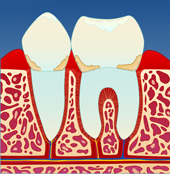

Mangelfullt renhold kan gi en overfladisk betennelse i tannkjøttet ( gingivitt ). Tannkjøttet blir da hovent og får en mørkere rødfarge. Det vil også blø ved berøring og føles ømt. Dette skyldes bakterier og mykt belegg som blir liggende langs tannkronen (I).

figur I figur II figur III figur IV

Dersom belegget ikke fjernes, vil det over tid forkalkes og bli hardt. Det er dette vi kaller tannstein. Tannstein forsterker betennelsen som fører til at benet rundt tennene brytes ned (II). På denne måten vil tannstein og bakteriebelegg kunne strekke seg stadig lenger ned langs rotoverflaten (III). Bentapet kan over tid bli så omfattende at tenner løsner og eventuelt må fjernes (IV).